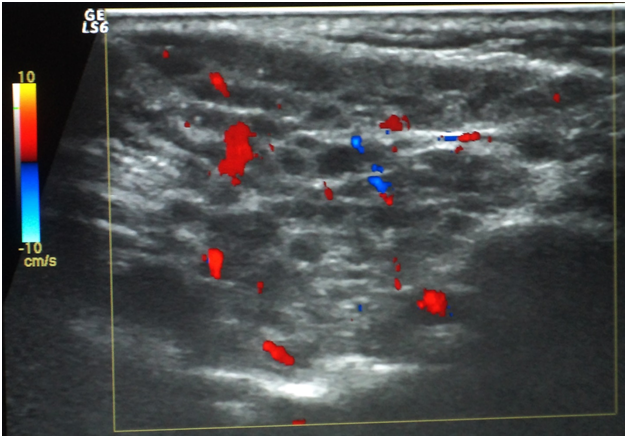

Histological findings

For Sjögren’s syndrome, salivary gland biopsy specimens have shown numerous lymphocytic foci in 4 mm2 (count > 50 lymphocytes per focus) within the glandular parenchyma. Acinar degeneration and few epimyoepithelial islands were detected. There was no substantial confluence of lymphocytes in a germinal-center-orientation within the submitted cases (Figure 3 & Figure 4). Focusing on characterizing any histopathological changes in GBS, the submitted cases of GBS revealed, in the asymptomatic glandular specimens, conspicuous perivascular and periductal infiltrations of neutrophils and macrophages. Moreover, vascularity was richer than that of normal mucosa whose vascular components were inconspicuous. Hemorrhagic spots, intervening extravasation of RBCs as well as dark acini, comparable to dust cells in smoking alveolitis, were also evident (Figure 5 & Figure 6).

Figure 3 Photomicrograph showing confluence of lymphocytic foci that infiltrate most of the architecture of the glandular parenchyma with acinar degeneration and epimyoepithelial proliferations. (H&E stained, Original magnification 10x).

Figure 4 A higher magnification of the previous photomicrograph in which a confluence of lymphocytes replaces the glandular parenchyma and degenerates the acini. (H&E stained, Original magnification 40x).